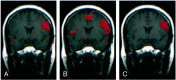

Background and purpose: Functional MR (fMR) imaging of word generation has been used to map Broca's area in some patients selected for craniotomy. The purpose of this study was to measure the reliability, precision, and accuracy of word-generation tasks to identify Broca's area.

Methods: The Brodmann areas activated during performance of word-generation tasks were tabulated in 34 consecutive patients referred for fMR imaging mapping of language areas. In patients performing two iterations of the letter word-generation tasks, test-retest reliability was quantified by using the concurrence ratio (CR), or the number of voxels activated by each iteration in proportion to the average number of voxels activated from both iterations of the task. Among patients who also underwent category or antonym word generation or both, the similarity of the activation from each task was assessed with the CR. In patients who underwent electrocortical stimulation (ECS) mapping of speech function during craniotomy while awake, the sites with speech function were compared with the locations of activation found during fMR imaging of word generation.

Results: In 31 of 34 patients, activation was identified in the inferior frontal gyri or middle frontal gyri or both in Brodmann areas 9, 44, 45, or 46, unilaterally or bilaterally, with one or more of the tasks. Activation was noted in the same gyri when the patient performed a second iteration of the letter word-generation task or second task. The CR for pixel precision in a single section averaged 49%. In patients who underwent craniotomy while awake, speech areas located with ECS coincided with areas of the brain activated during a word-generation task.

Conclusion: fMR imaging with word-generation tasks produces technically satisfactory maps of Broca's area, which localize the area accurately and reliably.